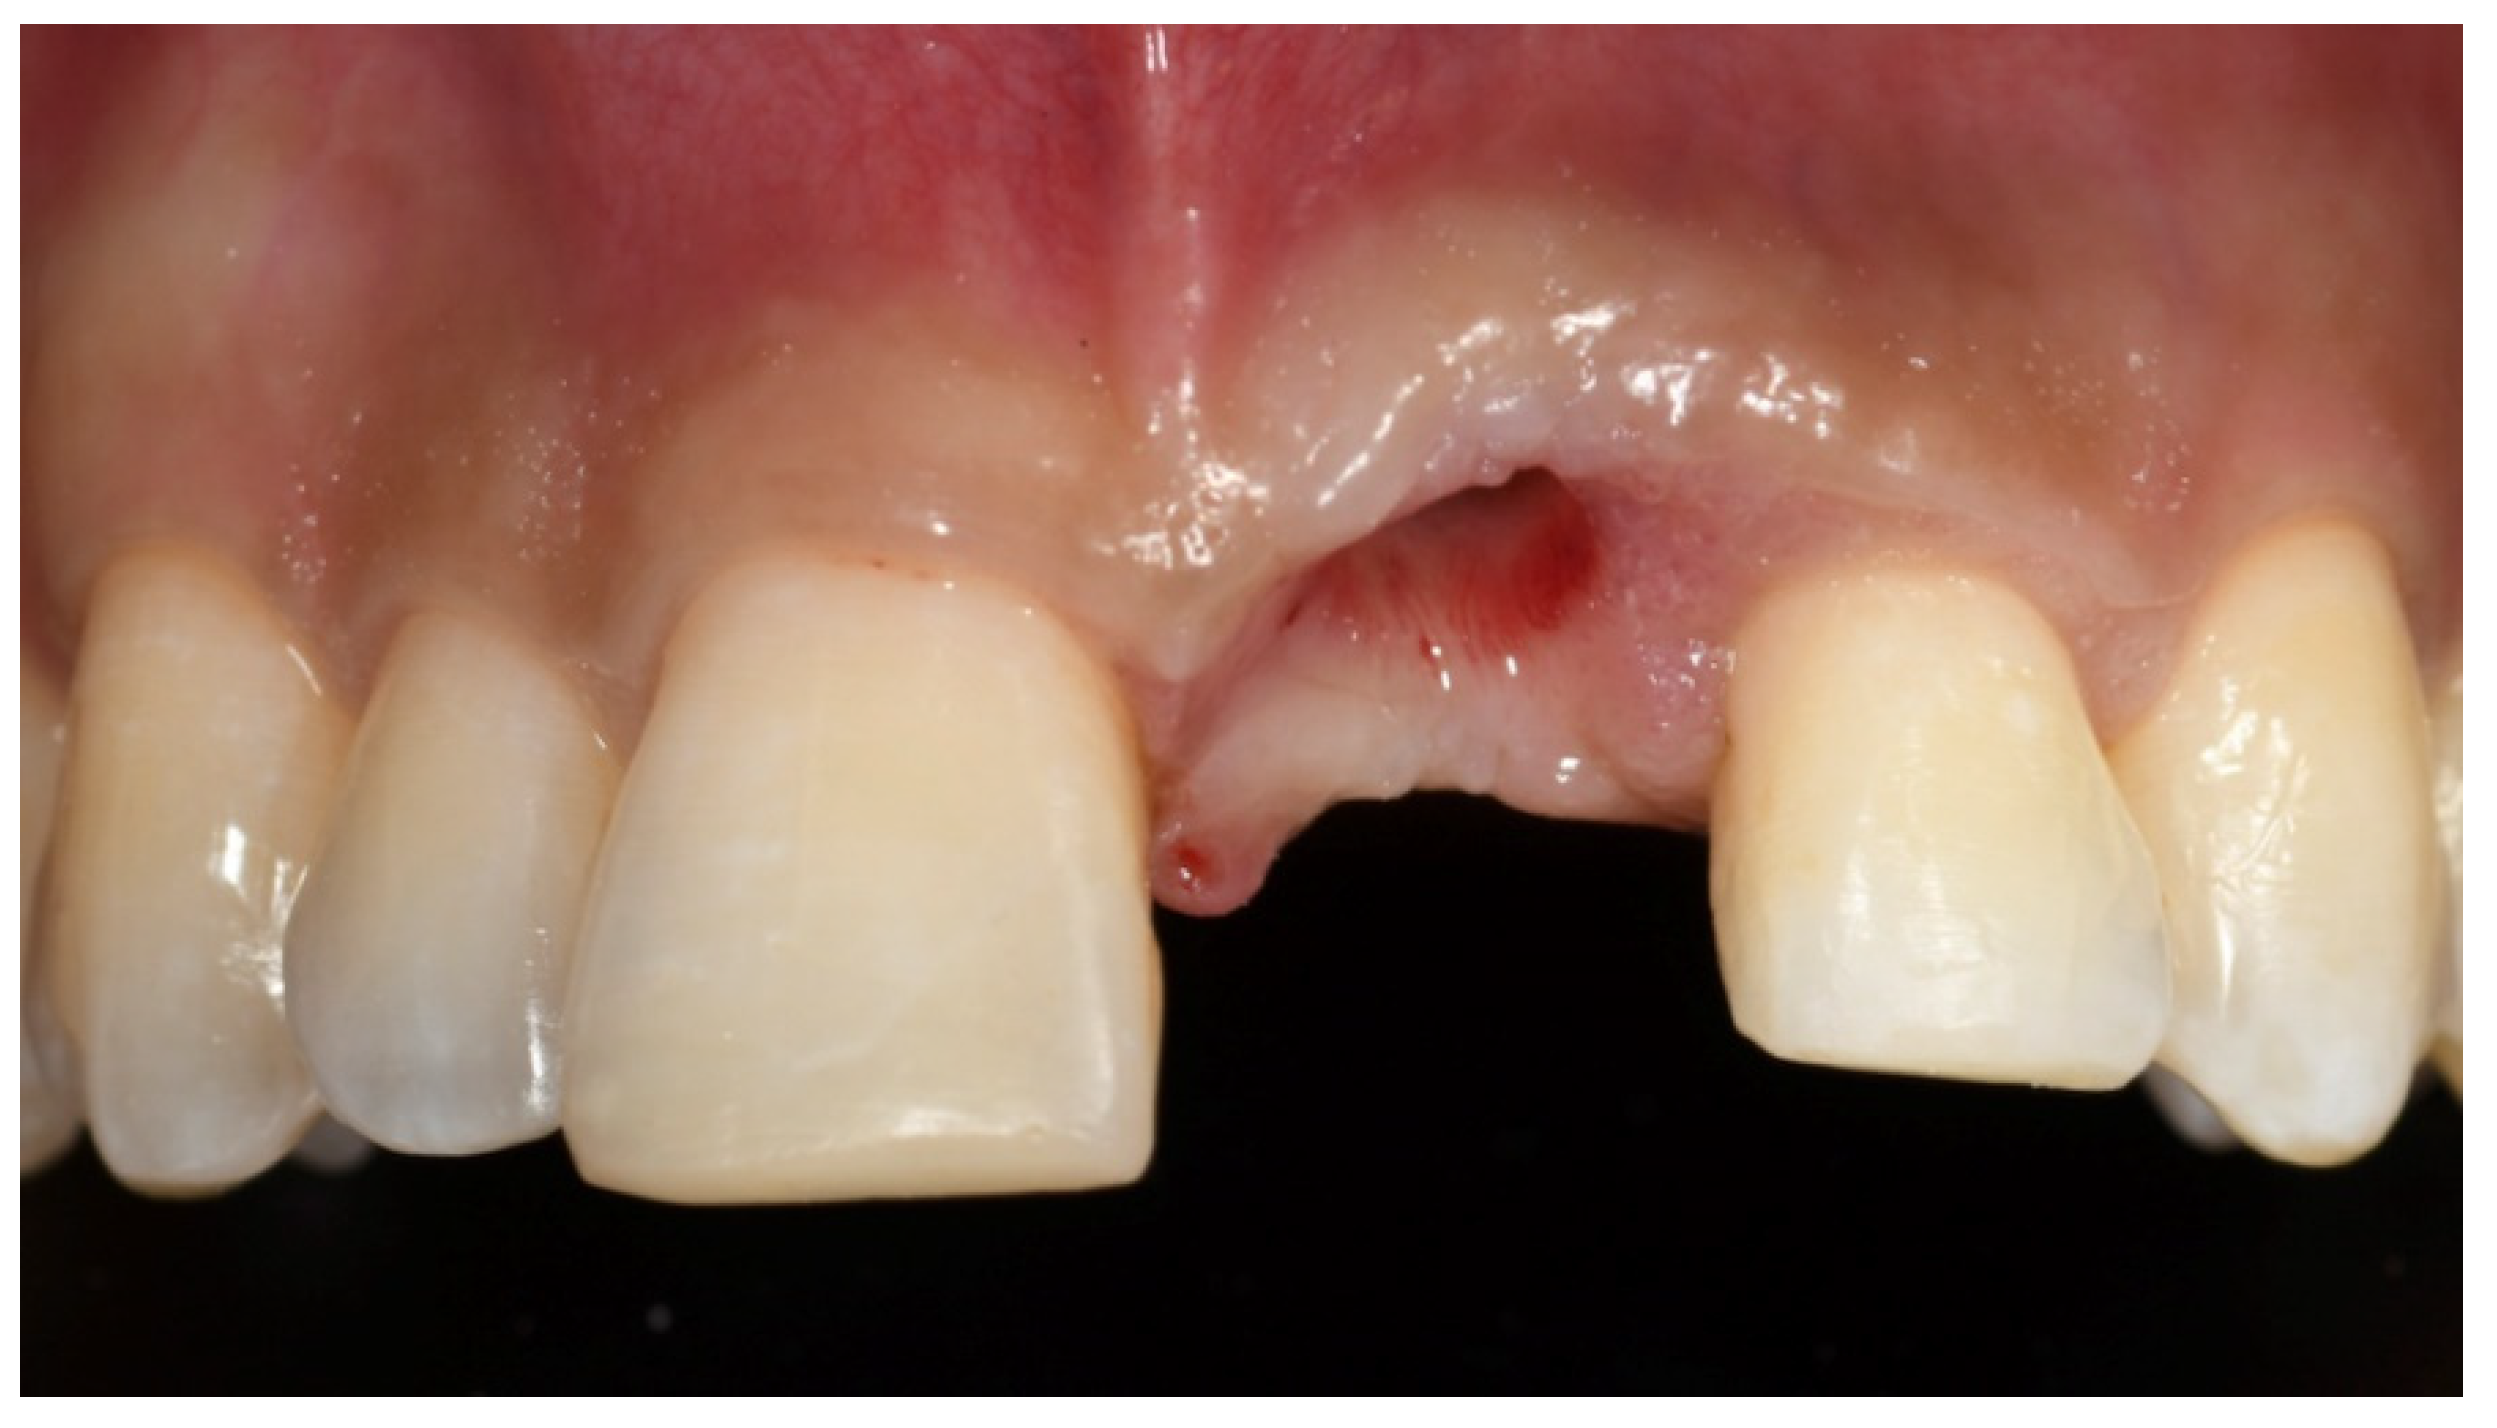

2. Case Presentation